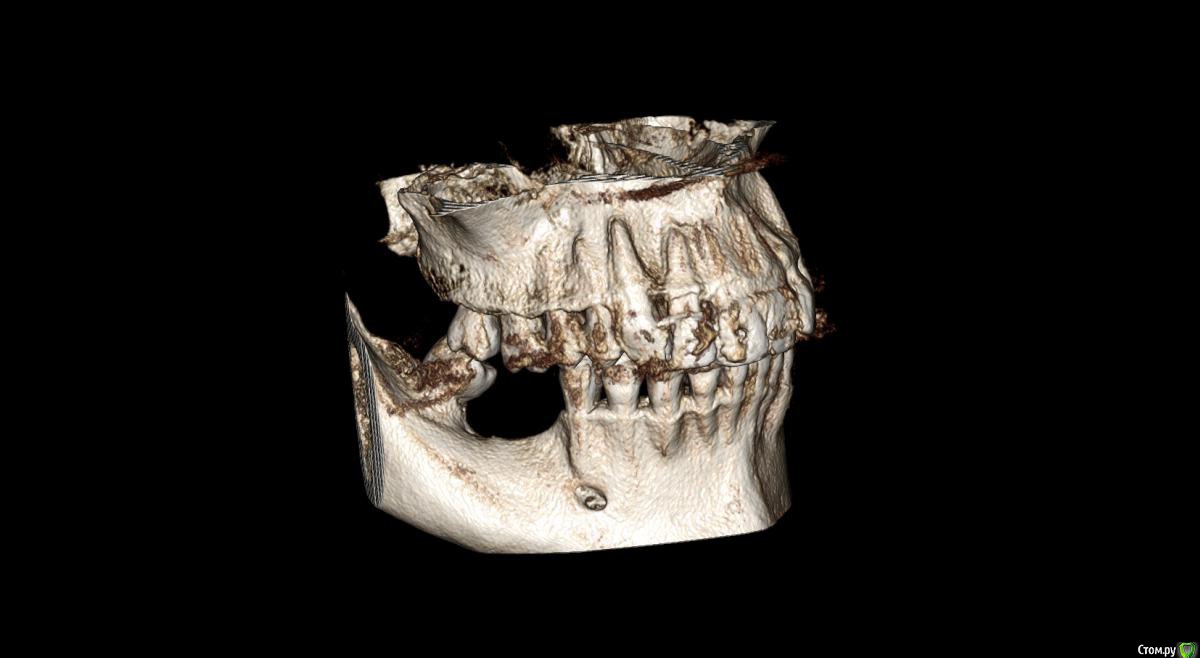

Господа как лучше тут поступить? поменьше бы рисков)

" всеводинэтап"крыша гаража" и латерализация отменяются)))

вижу вариант только с сеткой.

Из того что разобрал по срезам мне кажется можно медиально расщепить и притопить, дистально 4х6 поставить (астра, штрауманн...). Посмотрите, помещаются ли такие импланты. Травма меньше, быстрее и меньше рисков.